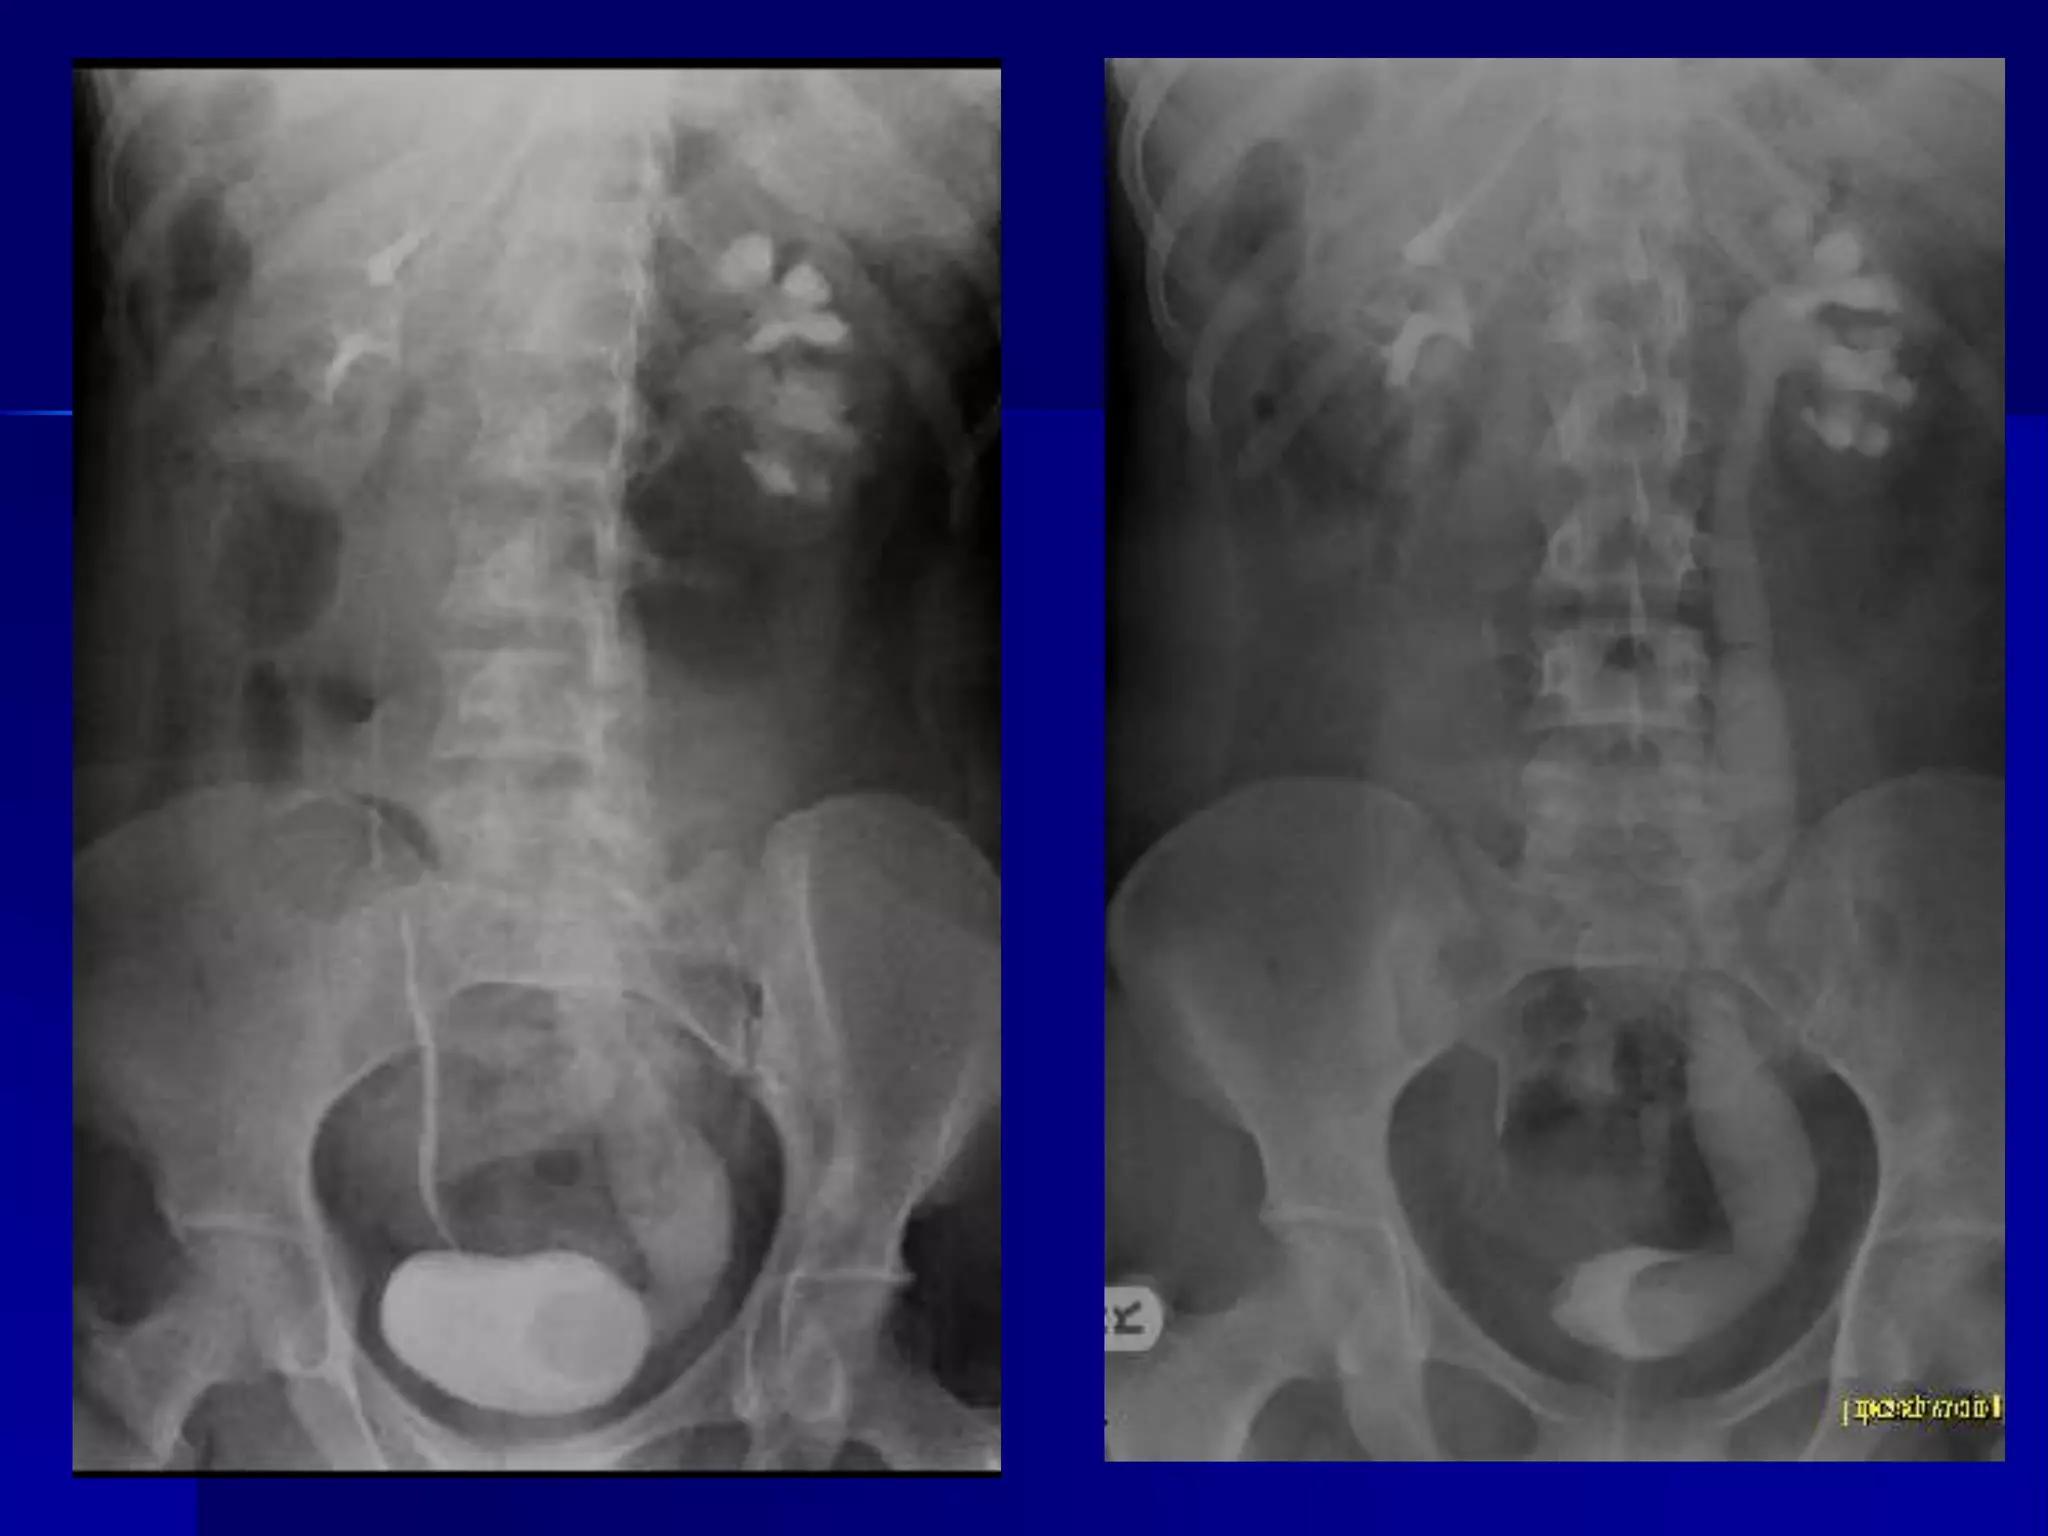

 Diagnosis

 Acute colonic pseudo-obstruction or

Ogilvie syndrome

 Differential

 Mechanical colonic obstruction

 Toxic megacolon

 Mesenteric ischaemia